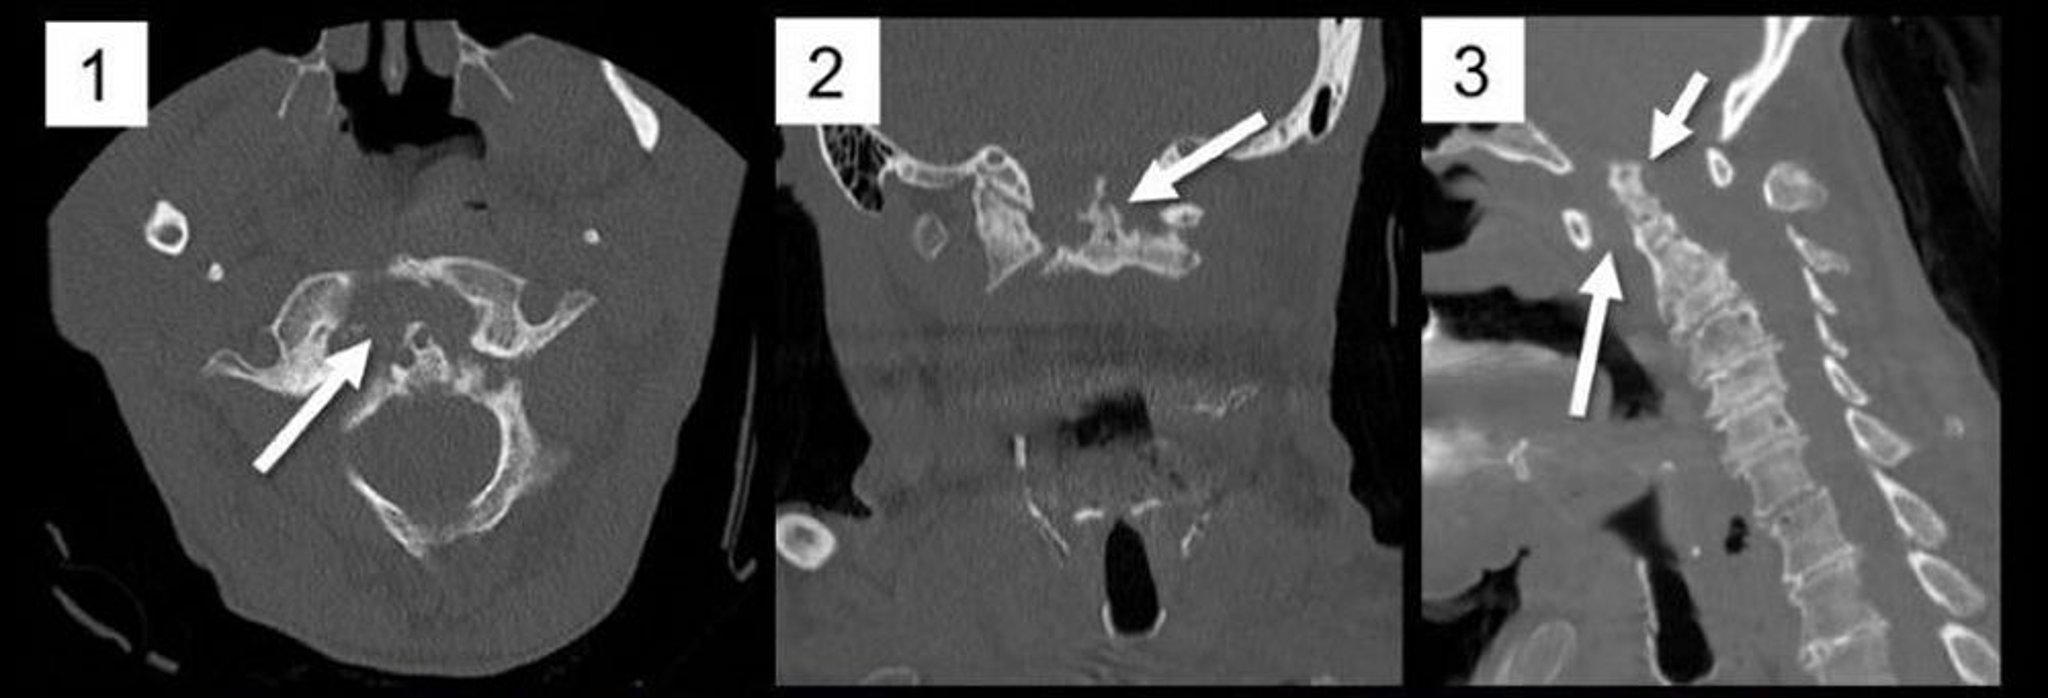

Subluxation axo-atloïdienne (atlantoaxoïdienne) (TDM)

Les reformations multiplanaires d'une TDM du rachis cervical dans les plans axial (1), coronal (2) et sagittal (3) montrent un élargissement marqué de l'intervalle atlantodentaire antérieur secondaire à la formation de pannus comme dans la polyarthrite rhumatoïde (1, flèche; 3, flèche longue), provoquant une subluxation postérieure et une impression basilaire du processus odontoïde C2 (3, flèche courte). Le processus odontoïde est nettement érodé (2, flèche), un signe typique de la polyarthrite rhumatoïde.

Image courtoisie de A. John Tsiouris, MD.